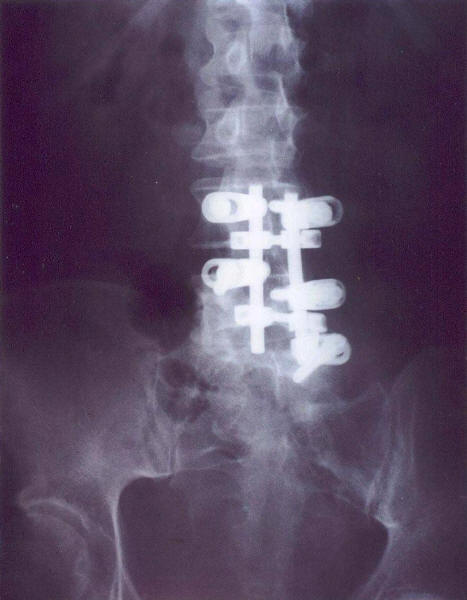

IP Artrodesis por lumboartrosis y laminectomía